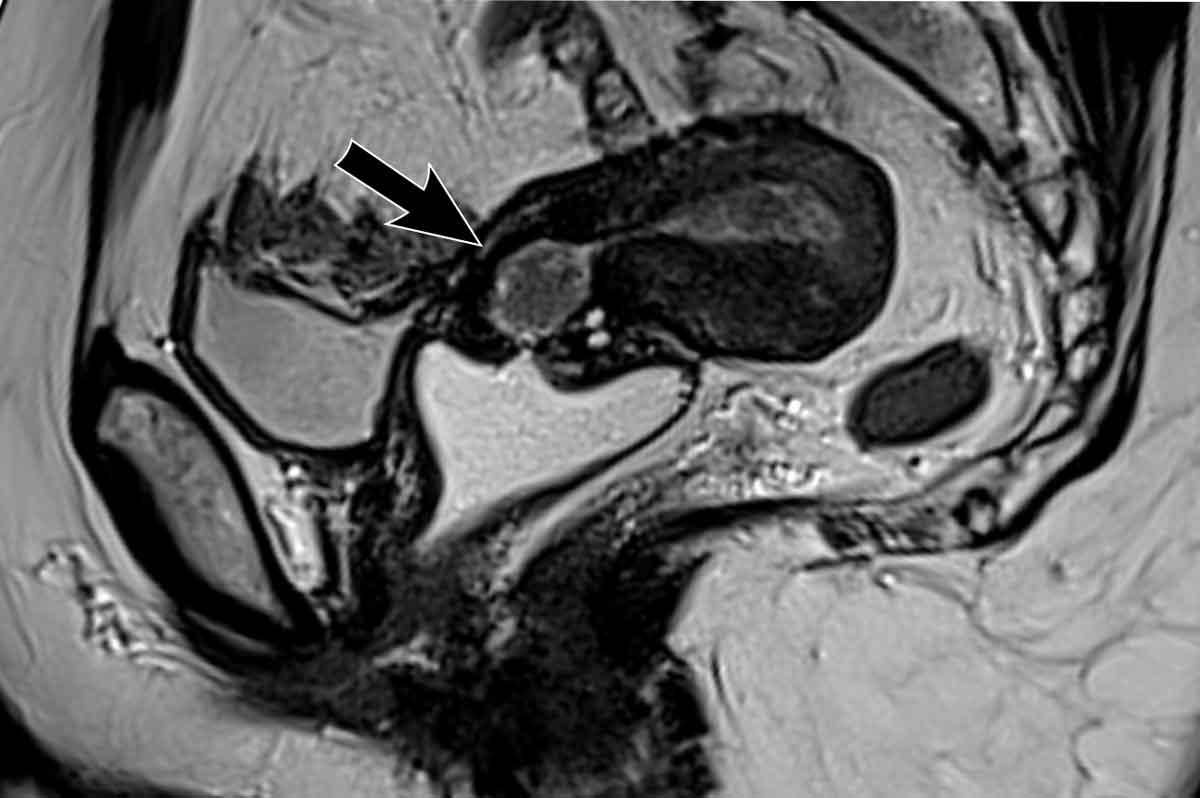

Xâm lấn ngoài tử cung (bao gồm xâm lấn bàng quang và trực tràng)

Đại đa số ung thư nội mạc tử cung còn khu trú trong tử cung tại thời điểm chẩn đoán, do các triệu chứng lâm sàng (xuất huyết) thường xuất hiện ở giai đoạn sớm.

Do đó, xâm lấn ngoài tử cung và xâm lấn thành bàng quang hoặc trực tràng hiếm khi được quan sát thấy trên MRI.

Khi phát hiện được, đây là bệnh giai đoạn tiến xa cần được ghi rõ trong báo cáo vì sẽ ảnh hưởng đến phương pháp phẫu thuật.

Hình ảnh

Đây là một ví dụ hiếm gặp về ung thư nội mạc tử cung tiến xa tại chỗ, phát triển vượt qua thanh mạc tử cung ở phía sau và xâm lấn đại tràng sigma (mũi tên).

Một ví dụ khác về khối u nội mạc tử cung (có thành phần thanh dịch trên mô bệnh học) biểu hiện xâm lấn mô đệm cổ tử cung lan rộng và một ổ lắng đọng khối u riêng biệt (di căn) trong thành âm đạo.